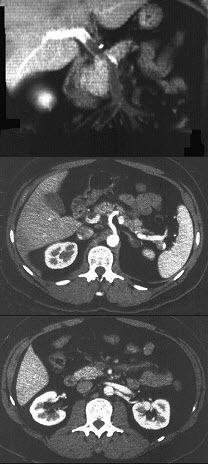

男性,40岁,半年前因双下肢麻木、发凉、疼痛于外院诊断血栓闭塞性脉管炎,近1周腹痛、腹胀,以中下腹为著,呈阵发性加剧就诊,行CT增强扫描,如图所示( )

A:胰头部略膨隆,内部密度不均。

B:门静脉及肠系膜肠系膜上静脉增宽。

C:门静脉及肠系膜静脉内见条形充盈缺损。

D:考虑为胰头癌。

E:考虑为门静脉及肠系膜内血栓形成。